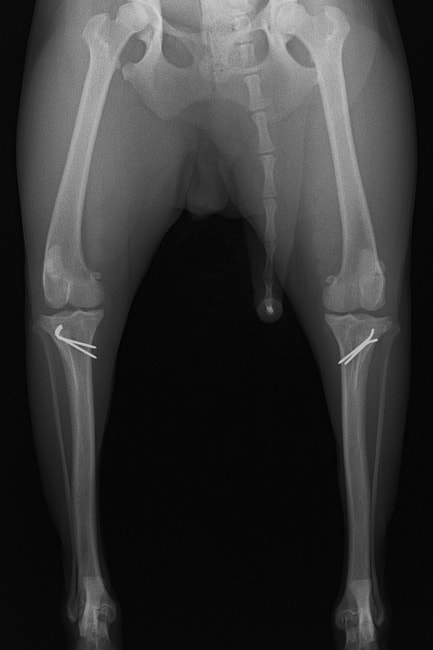

■ 症例24 キャバリア 7か月

左右膝蓋骨内方脱臼(左:グレードⅣ 右:グレードⅢ)

以前から左右後肢の跛行が認められ、整形外科学的検査・レントゲン検査により左右の膝蓋骨脱臼が認められた。症状が重度である左膝の膝蓋骨脱臼整復術を行った。外科手技は縫工筋及び内側広筋の解放、脛骨粗面の外側転位、滑車ブロック形造溝術、内外側関節方の縫縮を実施した。術後一か月時点で、左の膝蓋骨は安定しており経過は良好である。

本症例は成長期における重度の膝蓋骨脱臼であり、術後の再発の可能性もあるため、経過をしっかりと観察していく必要がある。また、今回手術を実施していない右膝に関しても経過を観察し、手術を検討していくこととする。